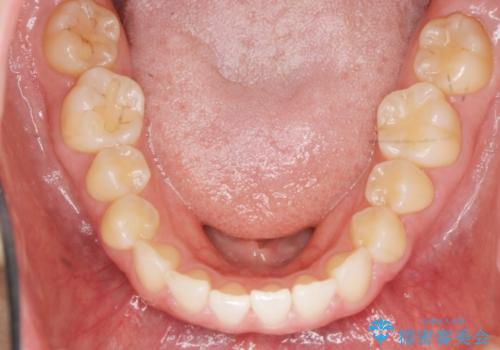

出っ歯に見える前歯の改善 部分ワイヤーとマウスピース矯正

- 出っ歯に見える前歯の改善を希望され、来院されました。

マウスピースでは改善の難しい歯の動きを部分ワイヤー矯正で整えたのち、奥歯の噛み合わせや細かい歯の並びをマウスピース矯正インビザラインで整えていきます。

最終的な前歯の並びに大変満足いただくことができました。